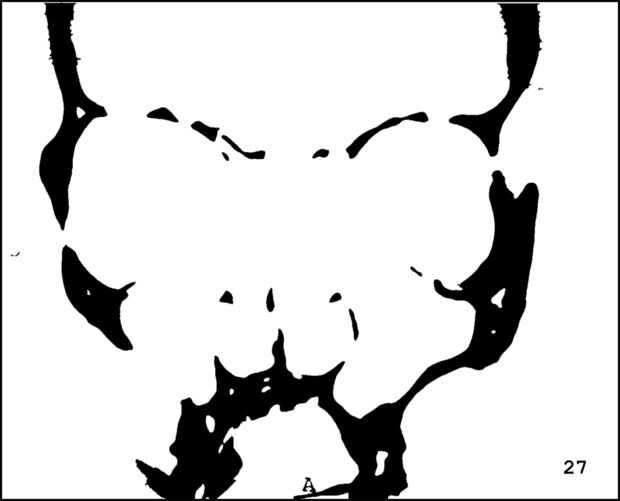

¡ Wow! Este fue por menos de 12 horas y tengo 1.000 visitas! Esto es sólo mi segundo instructable, así que estoy encantada. Decidí seguir adelante y publicar las imágenes que utiliza. Se trata de MRI de mi esposa, así que ella sólo puede tener lo mundos primer código abierto jefe. Mi lámpara utiliza solamente las primeras 16 capas, pero te di todos 34 que representa. Seguir adelante y usar estas imágenes, pero si lo haces, por favor me manden una imagen de lo que te ocurrió así que puedo hacerla sentir un poco famoso. ¡Que te diviertas!